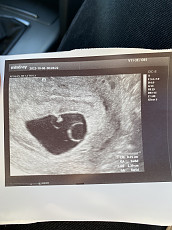

Galbūt yra kam buvę, kai trynio maišelis idealus, bet vaisiaus dar nemato? Ar yra …

Buvo man taip su antru nėštumu , bet buvo tik 6sav , pakartotinai ėjau 8sav ir jau matėsi vaikelis , plakė sirdute

Jei echo nuotraukytė dabar - tai, kad ir kaip liūdna, bet ne kokios tada prognozės... nes 8+ sav nėštume pagal jūsų TD pilvuką, jau embrionas su plakančia širdele t…

Vakar vakare buvau pas gyd. Leliukas nepadidėjo, tačiau stebuklingai per savaitę laiko pasirodė dar vienas trunio maišas! Tačiau gyd. pasitarus su kitu gyd. išrašė siuntimą į Šiaulių ligoninę išvalymui, nuvykus šiandien ryte apžiūrėjo jauna gyd. pabai maloni, tačiau net nespėjau sužinoti pavardės.Pažiūrėjus, kad 2 trynio maišai ir pamačius pokolkas tiek vieną embrioną vistiek pasiūlė dar palaukti 10-11 dienų, kad įsitikintų, jog viskas buvo padaryta ir negalėjo nieko padėti. Nutariau laukti ir užsiregistruoti pas gyd. po ~2sav. vis dar turiu viltį🤞🏻..